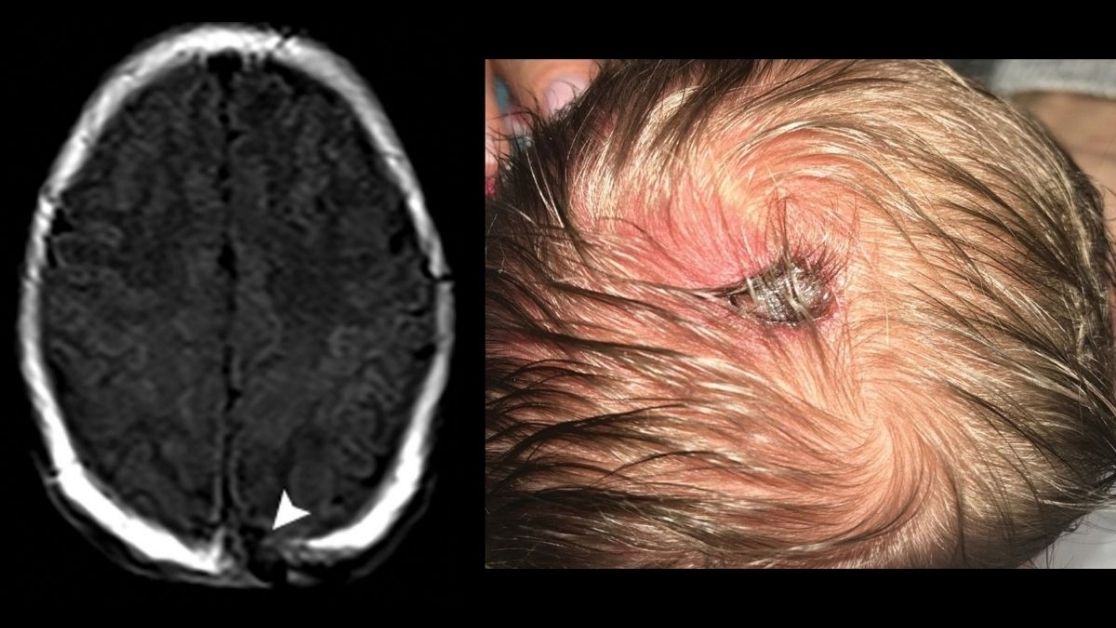

Calvarial lesions commonly present a diagnostic challenge. This article describes an imaging feature-based systematic approach to abnormalities of the calvarium with comprehensive illustrative examples. bit.ly/3kmERB1